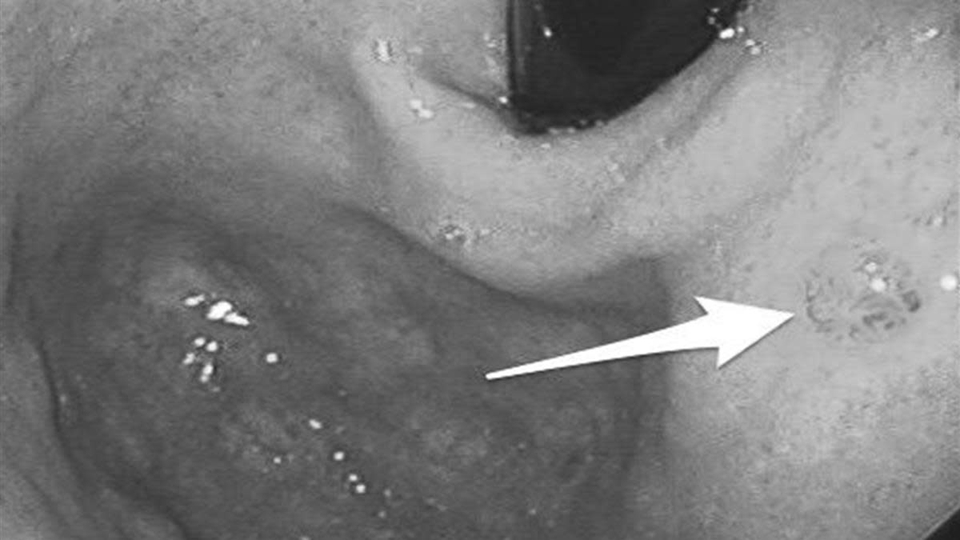

Cơ chế này chịu tác động của nhiều yếu tố. Nhiễm vi khuẩn Helicobacter pylori (HP), ăn mặn kéo dài hoặc thói quen sinh hoạt thất thường đều có thể làm suy yếu lớp bảo vệ niêm mạc dạ dày. Khi quá trình tổn thương và sửa chữa lặp lại nhiều lần nhưng không hoàn chỉnh, niêm mạc có thể xuất hiện “chuyển sản ruột” - một dạng tổn thương tiền ung thư.